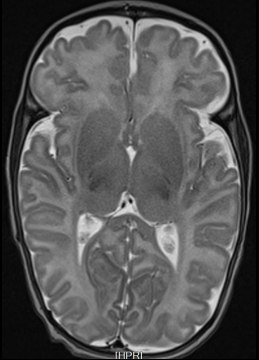

L’IRM pédiatrique

Les examens d’IRM peuvent également être réalisés chez les enfants. Toutes les zones anatomiques peuvent être acquises chez l’enfant comme pour l’adulte (cerveau, cœur, abdomen…).

Basée sur le principe de la résonance magnétique, cette technique nécessite un champ magnétique permanent. Elle n’est pas invasive, ni irradiante.